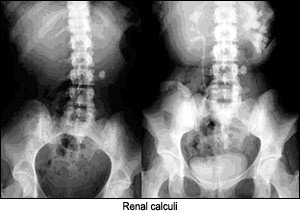

- lamellar; and

Rim-like appearance can be described as a wall of calcification surrounding a hollow structure, as in a renal cyst. Track-like or linear calcification indicates a tubular structure, as in the walls of the ureters or arterial walls. Lamellar calcification is formed in the lumen of a hollow structure, as in renal stones or stones in the gallbladder. Cloud-like calcifications are formed in a solid organ or tumor, such as a leiomyomas of the uterus or calcifications in the pancreas. Once the appearance of the calcification is apparent, the next step is to consider what anatomical structure is in that location. I am assuming one has ruled out the possibility of an artifact before considering a calcification as such.

The following images are representative of the four classic appearances of calcifications (rim-like, linear, lamellar, and cloud-like):

Renal calculi sometimes can be confused with mesenteric lymph node calcification or phleboliths, depending on location. The kidney calculi are frequently found in the lower end of the ureter, where it turns to enter the bladder. Other locations are the uretero-pelvic junction and where the ureter crosses the iliac vessels in the pelvis. An estimated 80 percent of all kidney and ureteral stones are visible on plain films. Unfortunately, this is technique-dependent.